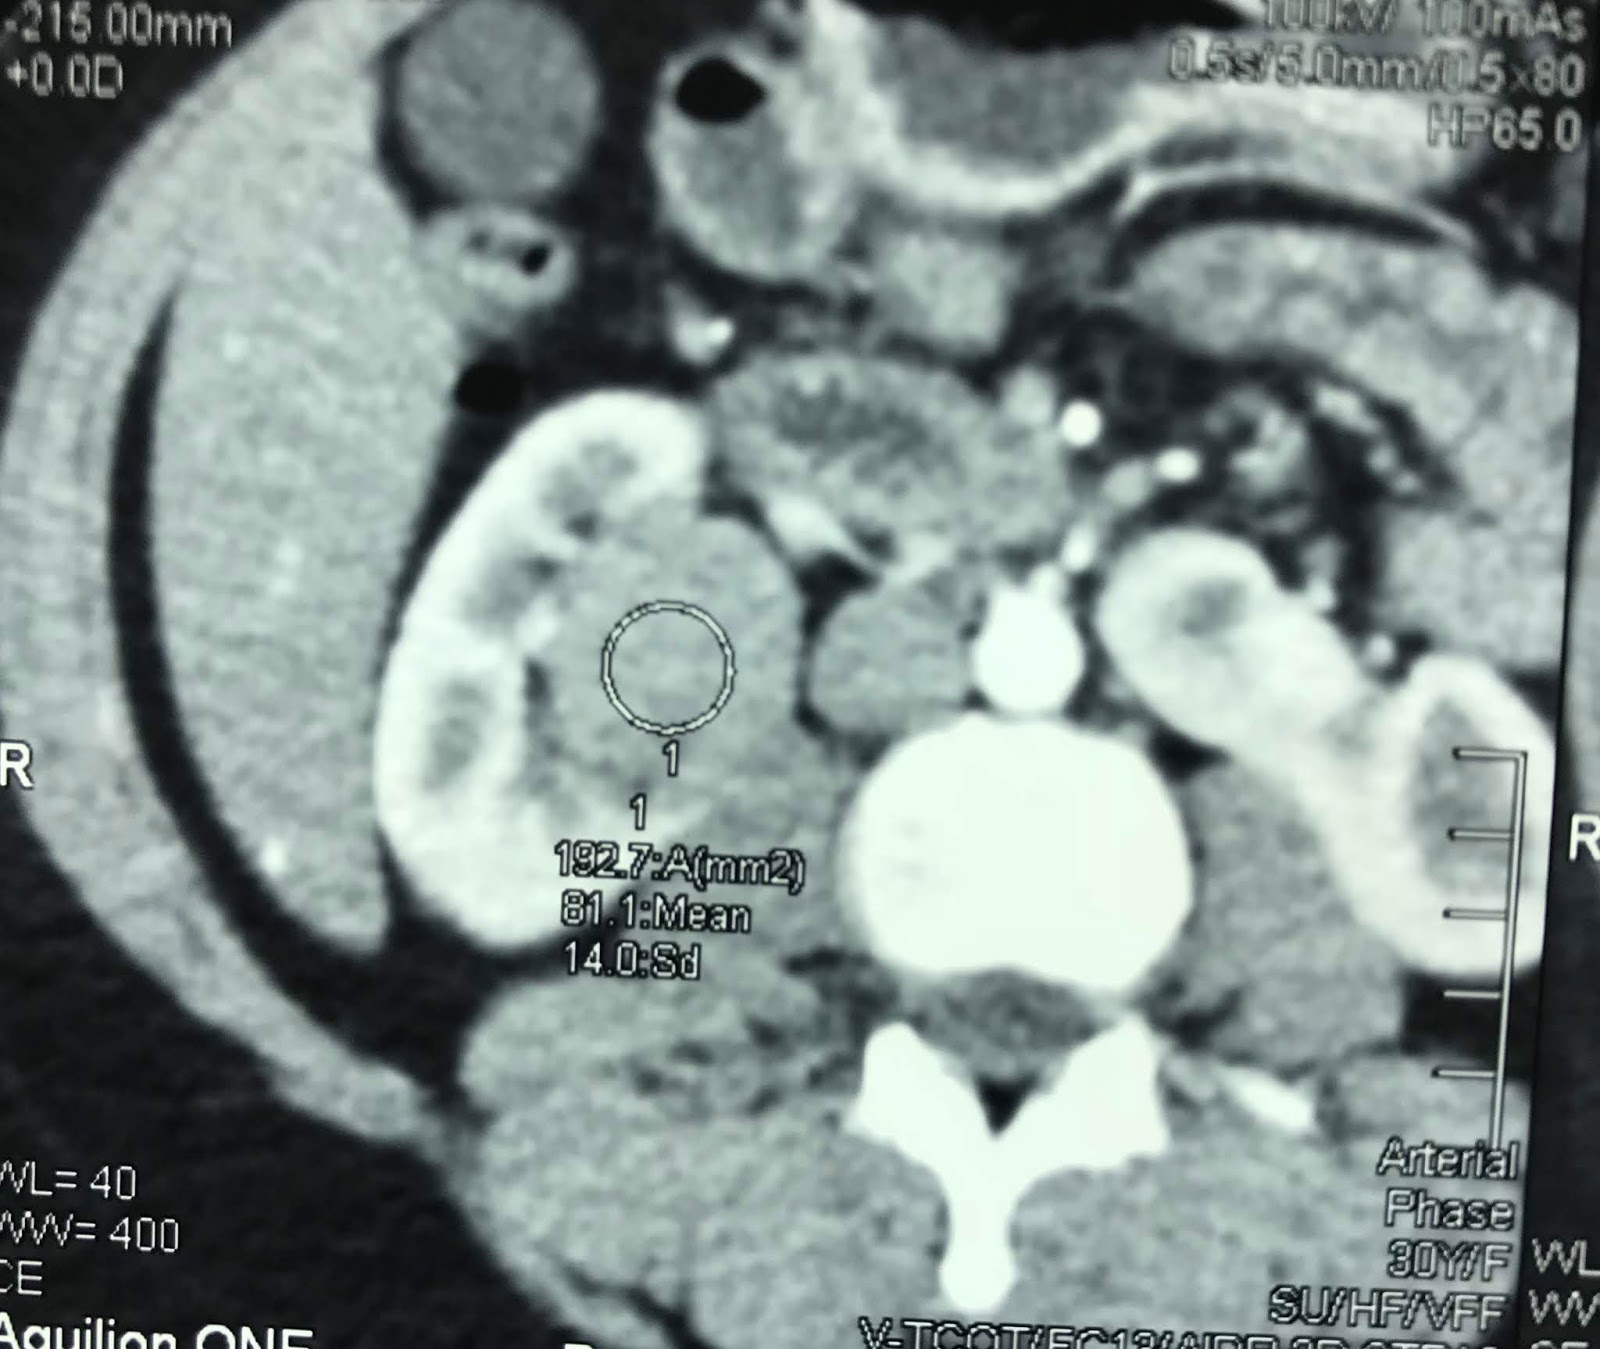

CT image of the tumor in the horseshoe kidney. Download Scientific Horseshoe Kidney Tumor — rcc is the most common neoplasm associated with horseshoe kidney. The tumor can localized at any part of the. — patients with horseshoe kidneys are at increased risk for upj obstructions, nephrolithiasis, vesicoureteral reflux, urinary tract infections,. We undertook this study to discuss various anomalies associated. surgical management of horseshoe kidney tumors is complex, but feasible. Horseshoe Kidney Tumor.

(a, b) Imaging findings of a right renal tumor in horseshoe kidney Horseshoe Kidney Tumor — patients with horseshoe kidneys are at increased risk for upj obstructions, nephrolithiasis, vesicoureteral reflux, urinary tract infections,. The tumor can localized at any part of the. horseshoe kidney (hsk) is a common renal fusion anomaly. We undertook this study to discuss various anomalies associated. — rcc is the most common neoplasm associated with horseshoe kidney. . Horseshoe Kidney Tumor.

Transverse sectional view of the tumor in the right horseshoe kidney on Horseshoe Kidney Tumor — patients with horseshoe kidneys are at increased risk for upj obstructions, nephrolithiasis, vesicoureteral reflux, urinary tract infections,. We undertook this study to discuss various anomalies associated. — horseshoe kidney is a rare condition where the kidneys fuse together at their base, forming a u or horseshoe. surgical management of horseshoe kidney tumors is complex, but feasible. Horseshoe Kidney Tumor.